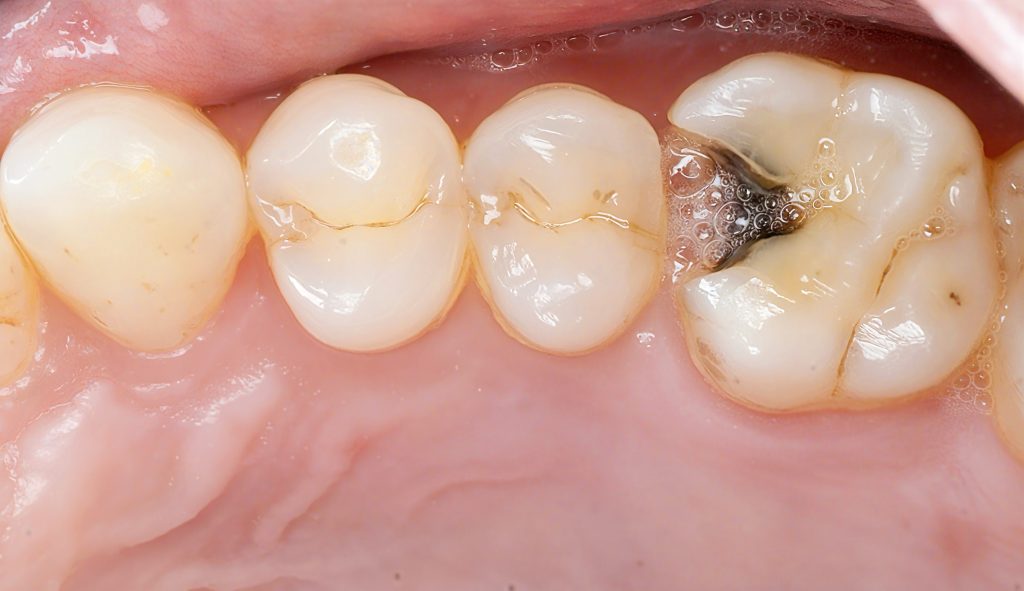

A lower posterior tooth presented with an incipient proximal lesion visible clinically and radiographically. The goal was simple: treat early disease with minimal preparation, preserve enamel, and rebuild a tight contact with a controlled adhesive workflow.

1. Pre-op evaluation

Bitewing radiographs show a small proximal radiolucency without pulpal involvement.

→ Perfect indication for a conservative Zerodont restoration.